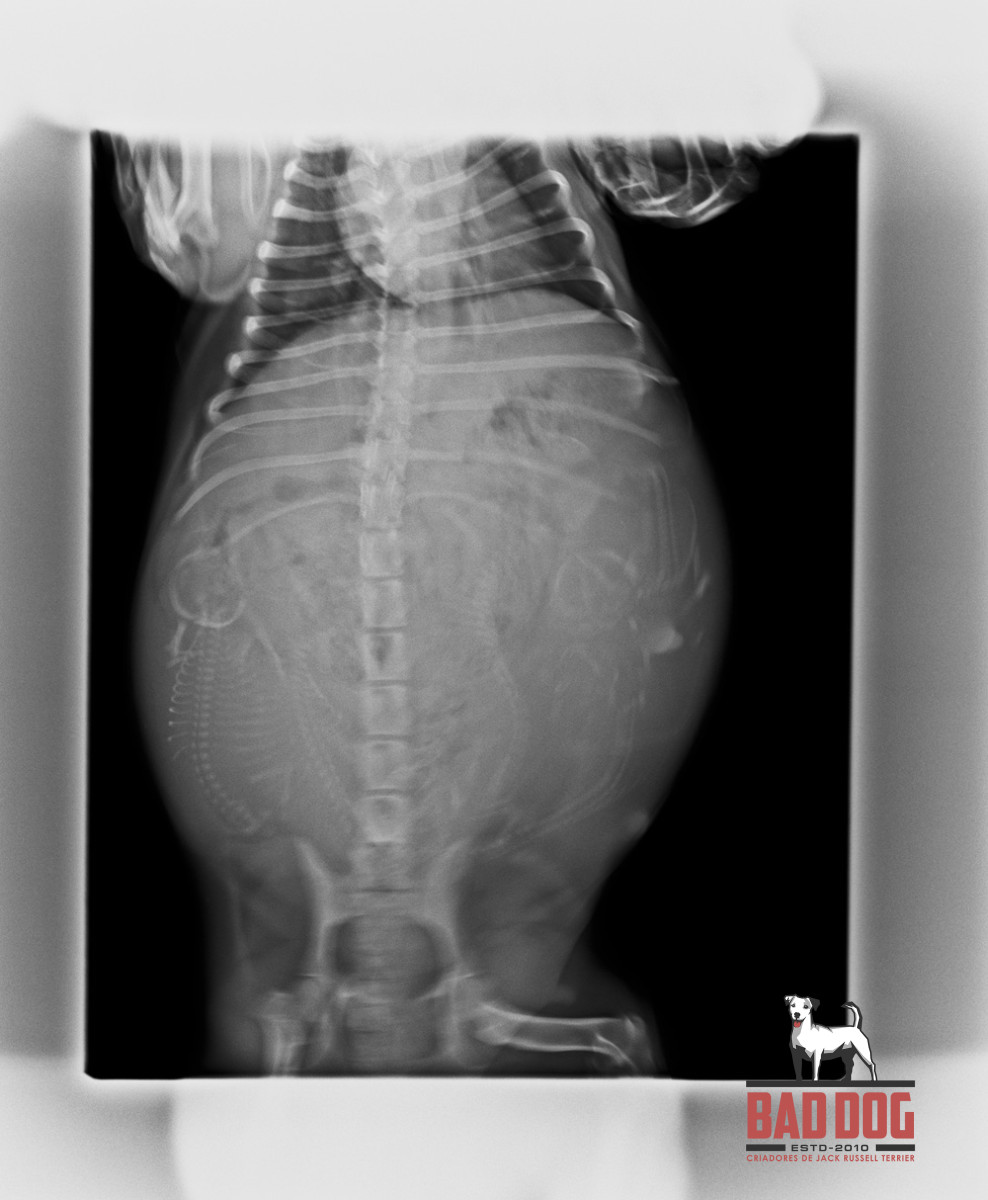

OMICRON2_TEASER_500X Ginja XRAY 2